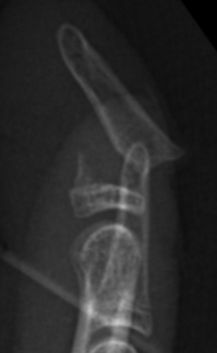

- Seymourfraktur - dislocerad Salter-Harris typ I eller II med luxerad nagel där nagelmatrix ligger interponerad i frakturen:

- Behandlas som öppen fraktur

- Antibiotika i.v.

- Snar öppen operation (inom 24 timmar) där man:

- reponerar interponat

- reponerar frakturen

- suturerar nagelanlaget

- fixerar frakturen med längsgående stift förbi DIP-led

Seymour-fraktur innan, under och efter operation